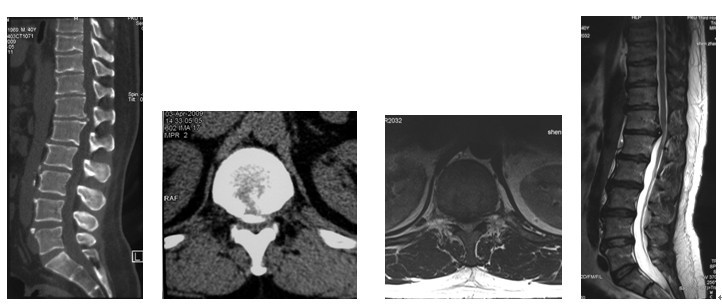

4. 典型病例:病例1,患者男性,40岁,司机。主因胸腰背部疼痛3年,肛周麻木、性功能减退并伴双足下垂2年,症状加重且二便肥力、无法工作1年入院。入院查体:一般情况良好,体胖、体重105kg。步态不稳,步行缓慢。胸腰段脊柱背部轻压痛,无放射。双侧股四头肌力IV级,双侧胫前肌力I级,双侧足下垂。鞍区感觉减退,无病理征。双侧跟、膝腱反射消失。血化验检查正常。X线平片显示T12~L1椎间隙明显变窄。CT显示T12~L1椎间盘突出并椎体后缘离断。MRI显示T12~L1椎间盘呈中央型突出,椎管狭窄,脊髓明显受压变形。入院诊断:T12~L1椎间盘突出症伴椎体后缘离断,马尾神经损害。术前检查完成后,在气管插管全麻下行上述经极外侧入路T12~L1椎间盘切除手术治疗,整个手术过程顺利,无术中及术后并发症发生,术后1周顺利出院。出院时,其双侧股四头肌、胫前肌肌力已分别恢复至V级和III级;鞍区感觉减退亦有明显好转。术后显示T12~L1突出之椎间盘及离断之椎体后缘已被完全切除,椎间融合器及椎弓根螺钉位置佳,脊柱局部生理曲度良好(图2a~2l)。病例2,女性患者,59岁。主因间歇性跛行,双下肢无力3年入院。入院诊断:T11椎体后上缘骨软骨瘤。以与病例1相同的术式行椎体骨软骨瘤的彻底切除(图3a~3l),无手术并发症发生,术后患者下肢症状明显改善。

图2a~2d. 典型病例1患者术前CT, MRI均显示为T12~L1椎间盘突出合并椎体后缘离断, 致椎管狭窄, 脊髓明显受压

图3a~3d. 典型病例2患者术前均显示为T11椎体后上缘骨软骨瘤,分明显突入椎管, 脊髓明显受压.